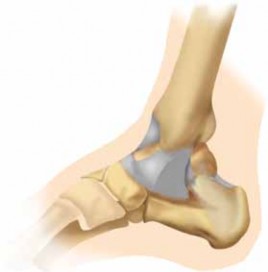

1. The ankle is a modified hinge joint, which relies on a con-gruently reduced mortise to provide optimal function.

2. Maintenance of normal tibiotalar contact is essential if one is to maintain function.

3. Surgical treatment of displaced, unstable ankle fractures centers on anatomic restoration of the bony and ligamentous relationships that make up the ankle mortise.

4. This chapter will focus on the treatment of a specific pattern of injury to the ankle, specifically the bimalleolar fracture pattern.

9. The lateral malleolus is the distal end of the fibula. It extends about 1 cm distal and posterior compared to the medial malleolus.